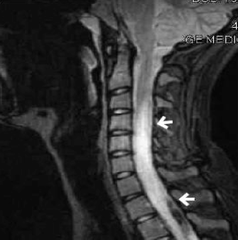

Myelitis

Inflammation fo spinal cord